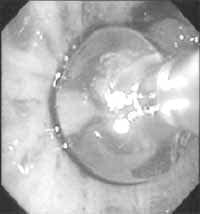

Figura 2. Tumor carcinoide bronquial típico, de localización central.

Si bien la primera aproximación diagnóstica invasiva a este tumor es a través de la fibrobroncoscopia, sólo un 60 – 77% de los tumores se ven a través de ésta (2,11,21). Corresponden a los tumores de localización central, tiene predominancia por el árbol bronquial derecho (2).

Dadas las características altamente vascularizadas de los tumores carcinoides, la decisión de tomar o no biopsias durante la broncoscopia es un dilema clínico dada la alta tasa de hemorragia derivadas de ésta. Así lo demostraron algunos estudios, como el realizado por Todd y cols, en el que se observaron 69 pacientes durante un período de 20 años, encontrando 6 casos de hemorragia grave posterior a la biopsia transbronquial, lo que hace que ésta no sea siempre posible e incluso contraindicada para ciertos grupos (7,25).

De otro lado, siendo el aspecto de características típicas; tumor hipervascularizado de superficie lisa, de localización central que puede obstruir total o parcialmente la luz bronquial; ha llevado a que el uso de la biopsia sea cada vez menor, y con las precauciones suficientes para evitar y/o controlar la complicación hemorrágica (1).

Figura 9. Tumor carcinoide endobronquial de localización central.

Cortesía Dr. Pedro Antonio Chaparro Mutis, Médico Internista –Neumólogo, Hospital Santa Clara E.S.E.